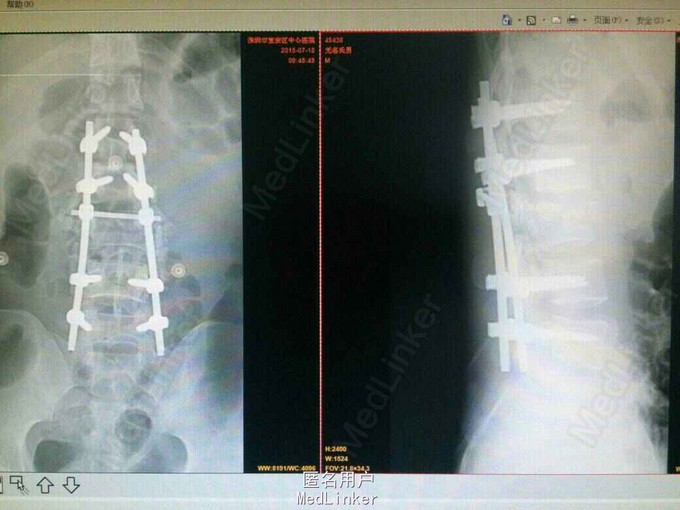

腰3椎体爆裂性骨折并双下肢不全瘫 手术后路椎管减压,椎弓根固定,腰3椎体骨折复位,后外侧植骨,椎管探查,硬膜修补。 术后脱水,激素,神经营养,二便及下肢功能康。 术后影像表现腰3椎体后移骨块复位。

一周后小便可自解,肌力:胫前:左III,右4级。 腰椎骨折后路減压可达到理想效。